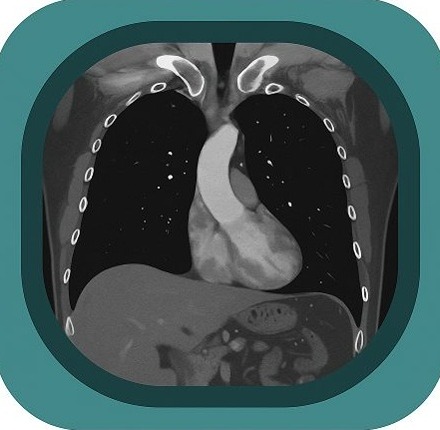

Explore full-body CT anatomy in 3 planes. Our high-resolution, carefully labelled images reveal micro-anatomy—ideal for radiologists, radiographers and surgeons.